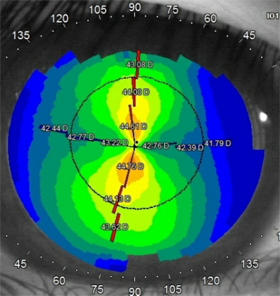

렌즈착용전·후 각막지형도의 변화

각막중심부가 솟아 있음

각막중심부가 평평하고 고르게 눌려있음

각막의 굴곡도, 굴절력, 크기 측정 및 각막 지형도 검사를 통하여 드림렌즈에 적합한 대상인지 확인 후 시험 착용을 진행합니다.

렌즈 착용 전 각막 곡률 반경, 각막 지형도, 각막 직경 측정 등 다양한 검사를 통해 알맞은 렌즈를 처방합니다.